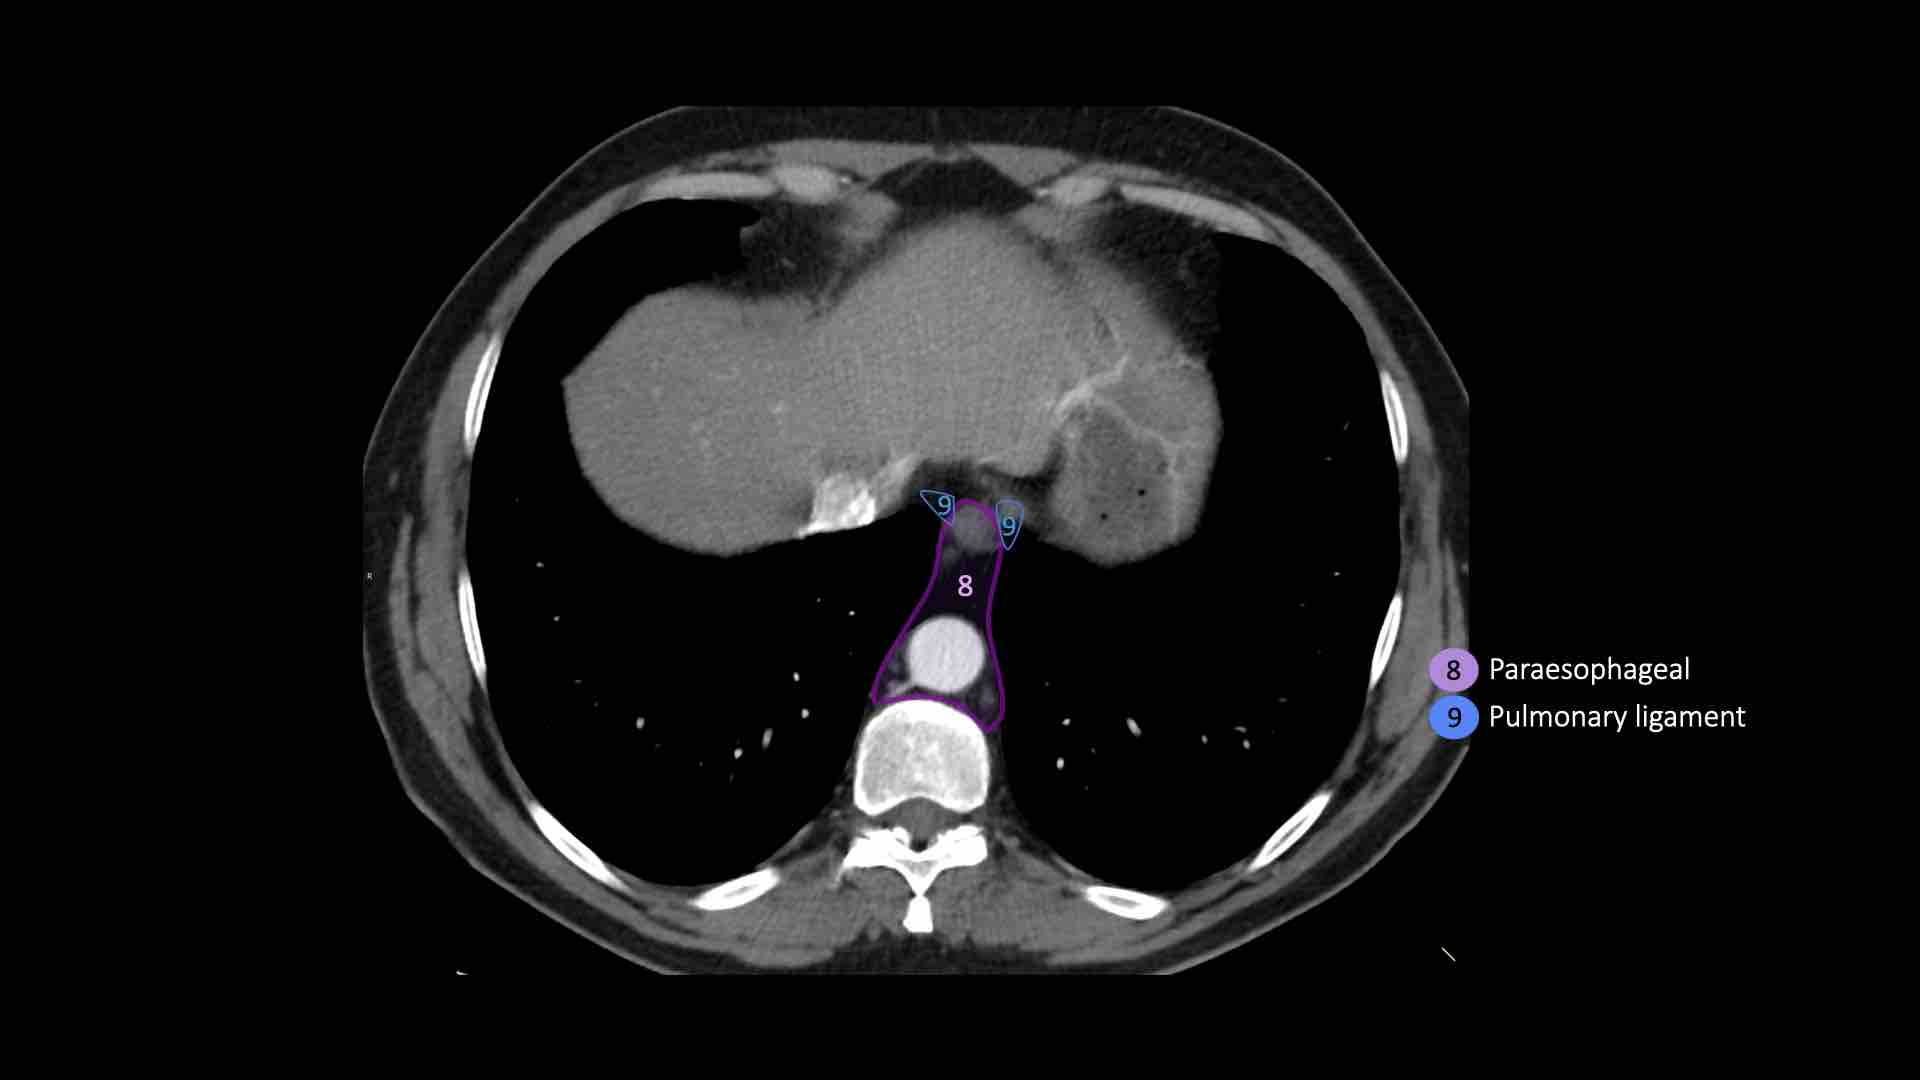

8. Cạnh thực quản

Các hạch nằm dưới carina.

9. Dây chằng phổi

Các hạch nằm trong dây chằng phổi.

8. Hạch cạnh thực quản

Các hạch này nằm bên dưới các hạch dưới carina và trải dài xuống đến cơ hoành.

9. Hạch dây chằng phổi

Hạch dây chằng phổi nằm trong dây chằng phổi, bao gồm các hạch ở thành sau và phần dưới của tĩnh mạch phổi dưới.

Dây chằng phổi là phần kéo dài xuống dưới của các nếp gấp màng phổi trung thất bao quanh rốn phổi.